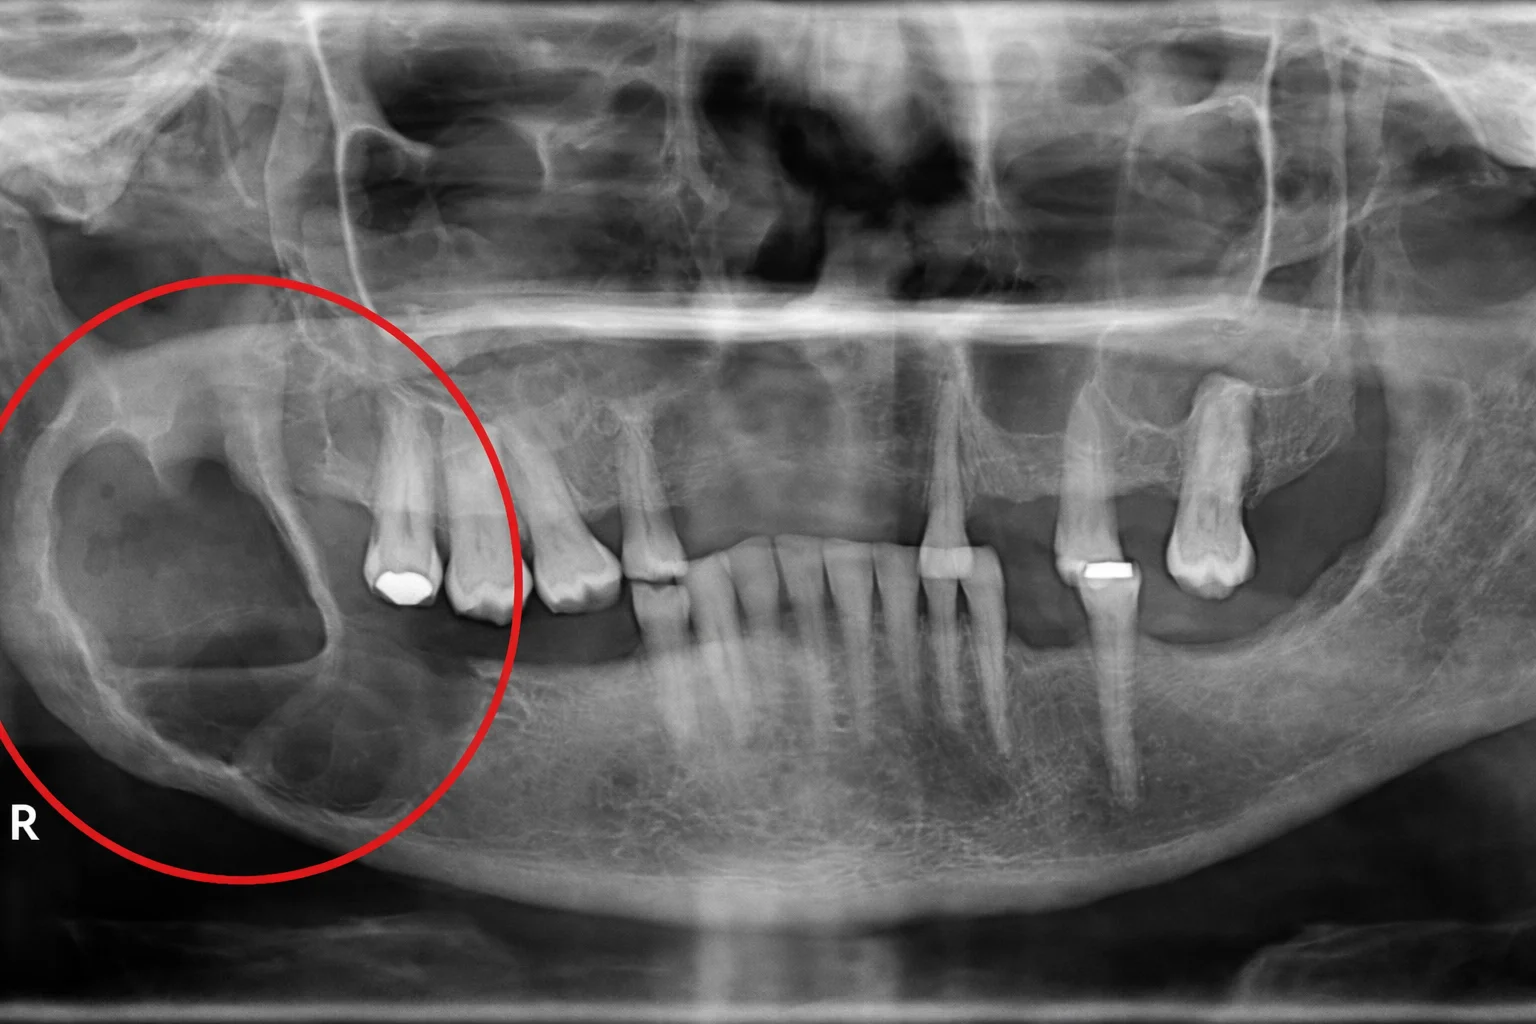

O termo patologias orais reúne diferentes lesões e alterações dos tecidos bucais e dos ossos da face. Isso inclui cistos, tumores benignos, alterações inflamatórias, lesões que precisam de biópsia e outras condições que pedem definição diagnóstica.

Nem toda alteração é grave, mas toda alteração persistente merece atenção. O mais importante é não tentar adivinhar o que é apenas pela aparência, já que lesões parecidas podem ter naturezas muito diferentes.